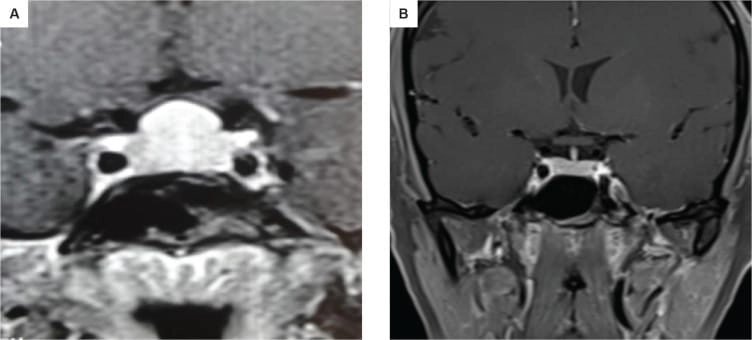

তবে পিটুইটারি হাইপারপ্লাসিয়া দেখা যায় প্রাইমারি গনাডাল, অ্যাডরিনাল বা হাইপোথাইরয়েডিজমের মত এন্ড অর্গান ইনসাফিসিয়েন্সিতে। বিশেষ করে, অব্যবহৃত প্রাইমারি হাইপোথাইরয়েডিজমে পিটুইটারি হাইপারপ্লাসিয়া পূর্বের ধারণার তুলনায় অনেক বেশি দেখা যায়। ২০১৯ সাল পর্যন্ত এরকম ১০৫টি কেস রিপোর্ট করা হয়েছে। এই ধরনের হাইপারপ্লাসিয়া গম্বুজ-আকৃতির (dome-shaped) হয়ে অপটিক কায়াজমাকে চেপে ধরতে পারে, যার ফলে অপারেশনের প্রয়োজন পড়তে পারে—যেমনটা আমাদের তৃতীয় কেসে ঘটেছিল।

চিকিৎসক তথা আবিষ্কারক সত্যম তিনটি কেসের বিষয় নিয়ে যখন তুলনা করতে নিলেন এবং পুরনো সৃষ্টি ঘাটতে শুরু করলেন তখন তিনি দেখতে পান সবগুলি ক্ষেত্রেই একই রকম সাদৃশ্য অর্থাৎ পিটুইটারি গ্রন্থি মাঝের অংশ এই গ্রন্থি দেখতে খানিকটা প্রজাপতির মতোই এবং তার মাঝের অংশের (প্রজাপতির দেহের উপরের অংশ মাথার মতই দেখতে) উপরের ভাগ সব ক্ষেত্রেই ডোমের মত বা গম্বুজ আকৃতির। তিনি এই ডোম বা গম্বুজ আকৃতি হওয়ার কারণ বিশ্লেষণ করতে গিয়ে দেখেন পিটুইটারির সামনের অংশ যেখানে থাইরোট্রপগুলো থাকে, যেখান থেকে এই টিউমারটি হয়। আর যখনই এটি বাড়বে তখন টমের মতনই তৈরি হবে। অর্থাৎ গম্বুজ আকৃতির। আর সেখান থেকেই ডোম-সাইনের উৎস অর্থাৎ আবিষ্কার।

MRI-তে এই হাইপারপ্লাসিয়া সাধারণত গম্বুজ-আকৃতির ও সমমিত হয় এবং হোমোজেনাস সিগনাল ইন্টেনসিটি দেখায়, যেখানে সাধারণ নন-ফাংশনাল পিটুইটারি অ্যাডেনোমা নানা আকার ও অসমতা নিয়ে দেখা যায়।

তাঁর দাবি, MRI-তে ‘DOME Sign’ থাকা এবং TSH বাড়তি থাকলে, সেটি হাইপোথাইরয়েডিজম-জনিত হাইপারপ্লাসিয়ার সম্ভাবনার কথা নির্দেশ করে এবং এই রোগীদের শুধুমাত্র লেভোথাইরক্সিন দিয়ে চিকিৎসা করলে পূর্ণ আরোগ্য সম্ভব।